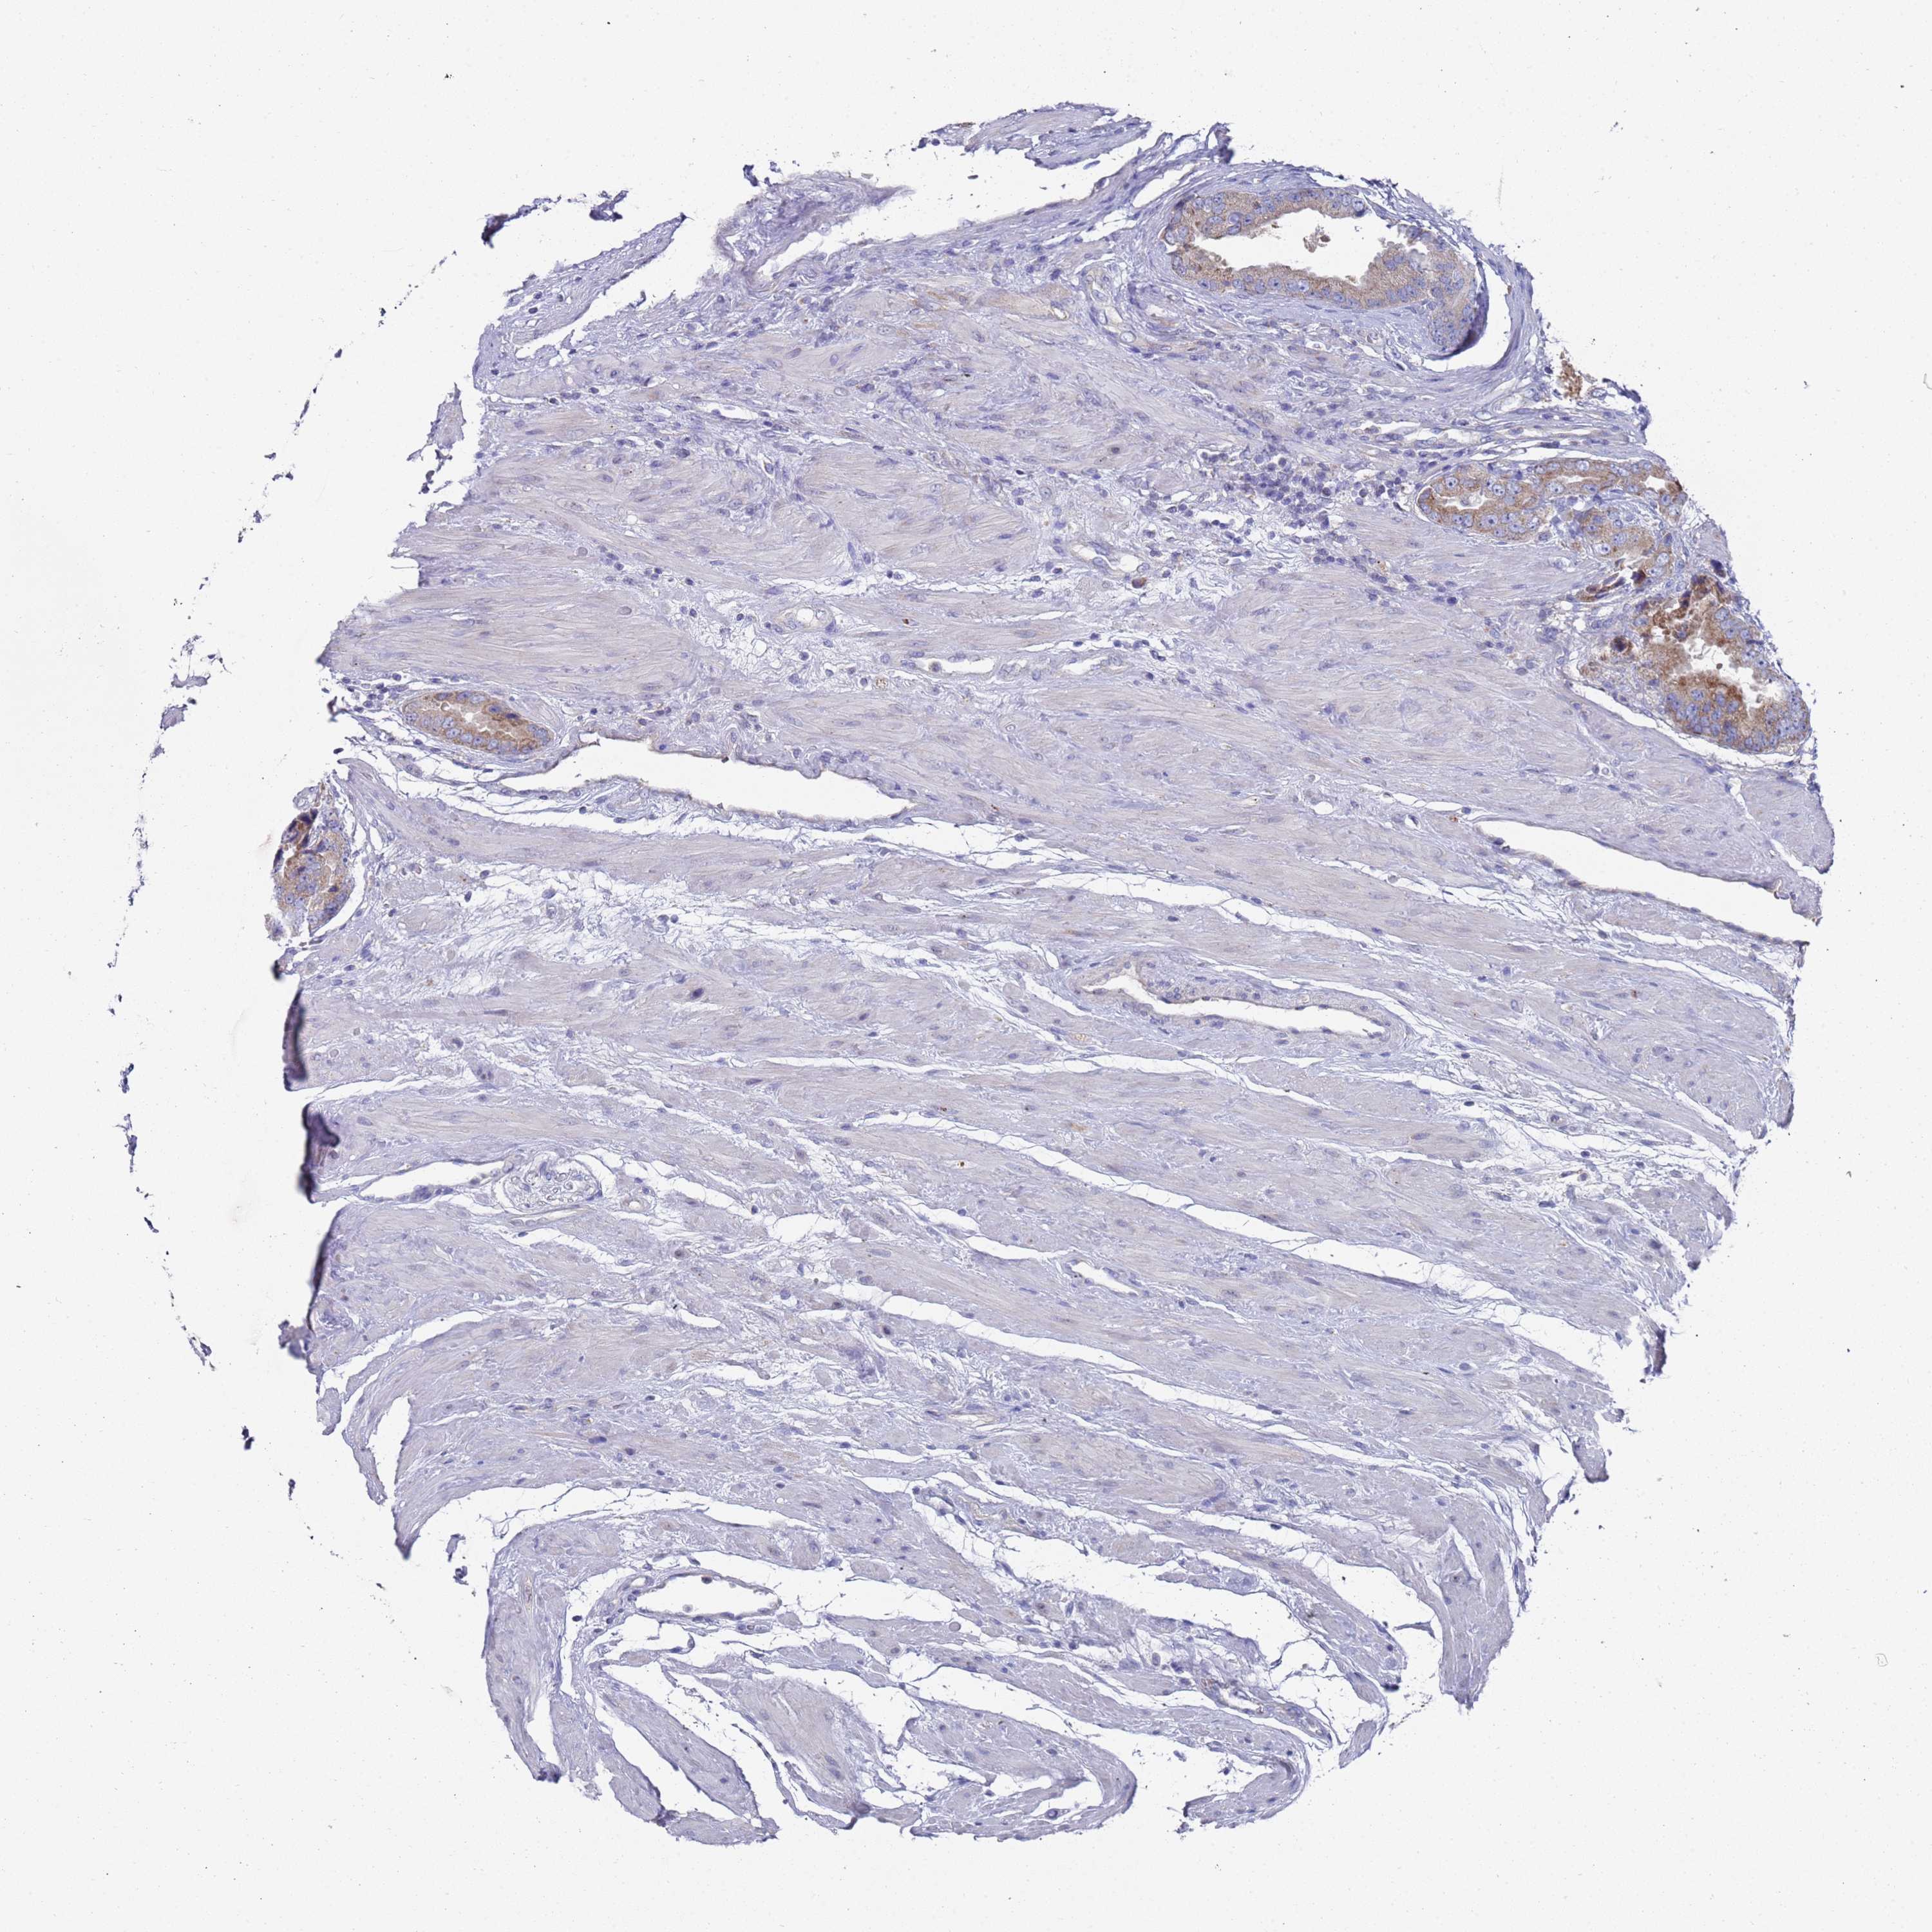

PROSTATE CANCER - Protein expressioni

A mouse-over function shows sample information and annotation data. Click on an image to view it in a full screen mode. Samples can be filtered based on level of antibody staining by selecting one or several of the following categories: high, medium, low and not detected. The assay and annotation is described here.

Note that samples used for immunohistochemistry by the Human Protein Atlas do not correspond to samples in the TCGA dataset.

Antibody stainingi

Antibody staining in the annotated cell types in the current human tissue is reported as not detected, low, medium, or high, based on conventional immunohistochemistry profiling in selected tissues. This score is based on the combination of the staining intensity and fraction of stained cells.

Each image is clickable and will lead to virtual microscopy that enables deeper exploration of all samples and also displays staining intensity scores, fraction scores and subcellular localization as well as patient and tissue information for each sample.

Antibody HPA021453

Antibody HPA045649

Staining

High

Medium

Low

Not detected

Intensity

Strong

Moderate

Weak

Negative

Quantity

>75%

75%-25%

<25%

None

Location

Nuclear

Cytoplasmic/membranous

Cytoplasmic/membranous,nuclear

Adenocarcinoma, NOS

Adenocarcinoma, High grade

Adenocarcinoma, Low grade